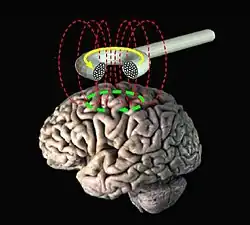

Compared to invasive stimulations, non-invasive stimulations are deemed to be safer and more ethical in terms of the procedures as the process occurs externally through shockwaves delivered through a piece of equipment (Kelly et al., 2019). It is also considered to be more practical and convenient about the reliability of the measure – with some procedures having to be repeated in a given length of time between sessions (Dubreuil-Vall et al., 2019). Examples include transcranial direct stimulation (tCDS) (as shown in figure 1) and transcranial magnetic stimulation (TMS) (Grazzi, 2015).

Although there are various types of neurostimulation procedures, not all can apply to the regulation of emotions. It is perceived that the use of non-invasive neurostimulation can be more efficient to use for procedures involving modulation of the emotional brain (Kelly et al., 2019). Two of the most commonly used neurostimulation devices are transcranial magnetic stimulation (TMS) (as seen in figure 3) and transcranial direct current stimulation (tDCS) – which might appear to be the same for some but has their distinctiveness (De Raedt et al., 2015).

Both procedures (TMS and tDCS) involve the use of equipment on the patient’s head and can both be used for situations of depressive and anxious symptoms but the procedures differ in how long and intense the electric signals are. De Raedt et al. (2015) stated that TMS activates the neurons themselves but tDCS can only control the action potentials (start-up) of neurons. However, both procedures are still effective as a treatment for some mental illnesses.

For TMS, a metal rod with a magnetic coil at the end is used to stimulate neurons by generating electrical signals to allow the production of neural synapses (De Raedt et al., 2015). With tDCS, electrode patches are placed into several specific parts of the scalp to match with the parts underneath in the brain to ensure equal distribution of electrical signals (De Raedt et al., 2015).

Both of the procedures are conducted just above the patient's head which creates a magnetic field for the primary electrical current to reach the neurons in the brain. There needs to be a second electric current to be conducted for action potential (see figure 4) to happen and signals the neurons to release the neurotransmitter that the patient is lacking (Cirillo et al., 2019). In parts of the brain that has a disparity of emotional responses, neurostimulation will be able to balance it out by "forcing" the neurons to release neurotransmitters through the emission of electric current or voltage and stabilise the level of emotions (De Raedt et al., 2015).